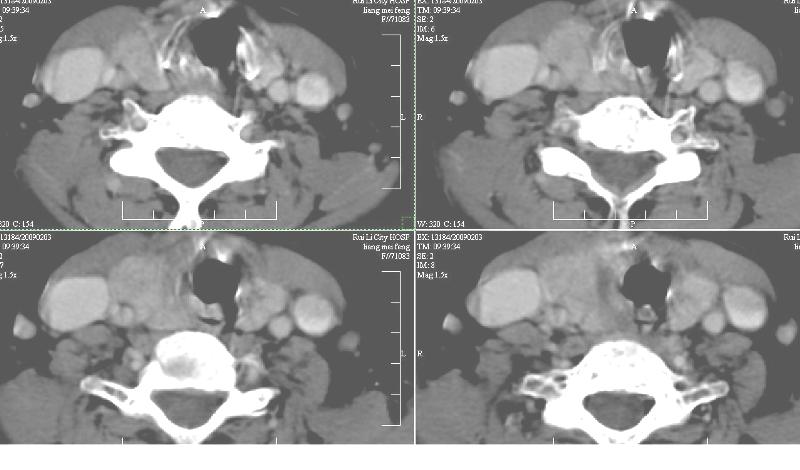

增强:1、双侧甲状腺肿。2、平扫甲状腺内多发占位病变,增强显示不清楚,境界欠清,请结合临床考虑甲状腺瘤。

右侧甲状腺占位及右侧淋巴结肿大,考虑甲状腺癌!期待结果!

强化效果一般,未见明显恶性征象。

1)弥漫性甲状腺肿。2)甲状腺多发性腺瘤?